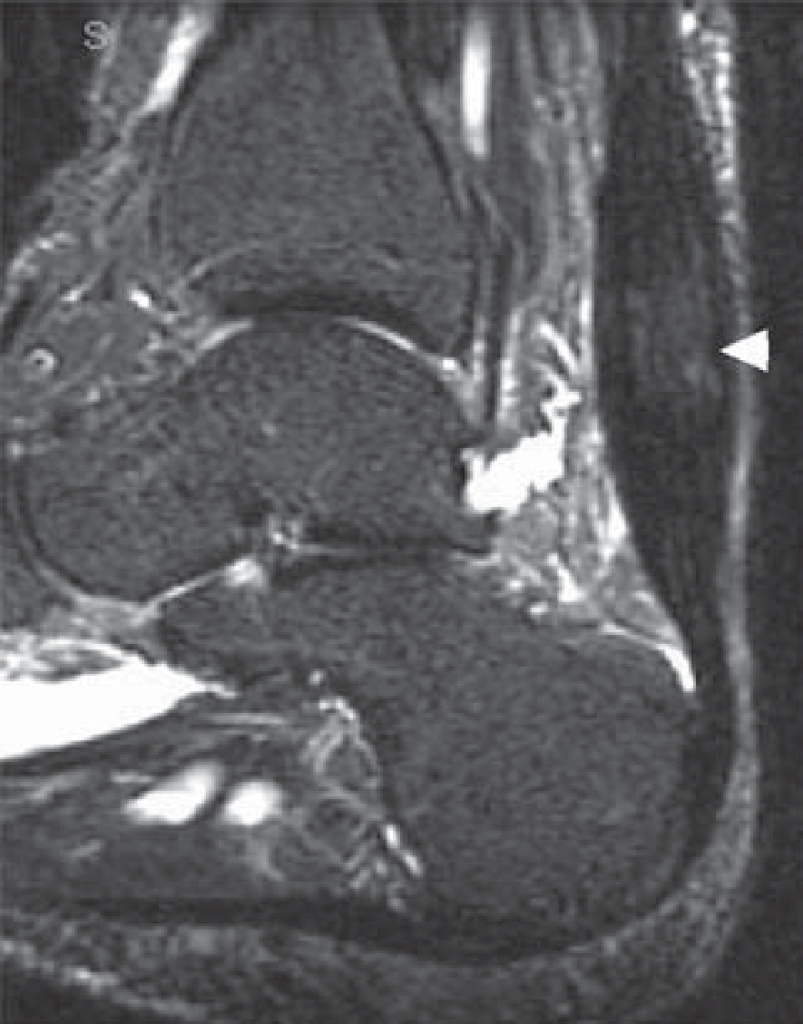

Non-insertional tendonitis is inflammation in and around the Achilles’ tendon higher up the leg from the heel.  It most commonly occurs in association with running and jumping sports where forces in the Achilles’ tendon can increase to 10 times body weight. It can also occur in association with overuse syndromes, postural problems, poor footwear, or an underlying inflammatory condition that may affect multiple joints in the body.

Patients usually experience pain approximately 2-6 cm further up the leg from the heel. This may even occur at rest and/or at night. Over time, the tendon becomes thickened and an abnormal lump may be felt in the same area.

Keyhole surgery is not possible for this condition, with a large incision needing to be made at the back of the lower leg. The diseased tendon and surrounding tissue is removed and the remaining healthy tendon is refashioned to bridge the defect.

Often in order to assist the achilles to recover a near-by tendon is harvested to reinforce the strength of the Achilles’ tendon. This tendon normally functions to flex the big toe. It is not often missed as other muscles take over its function.